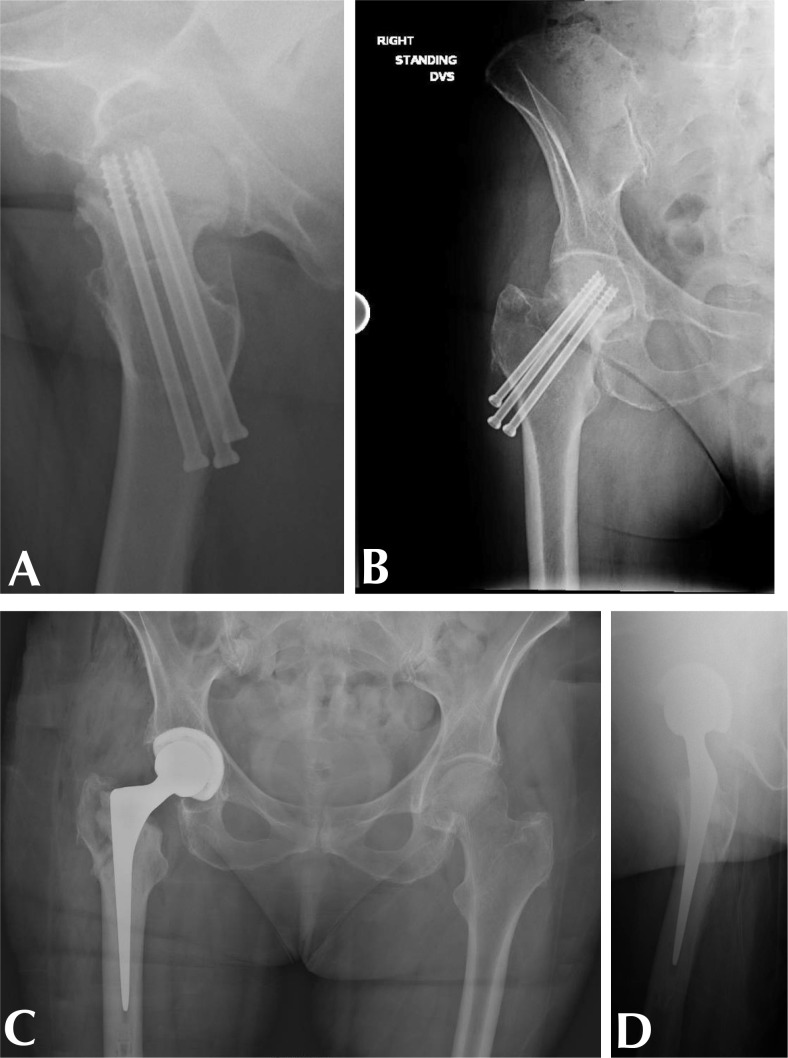

Abstract Image